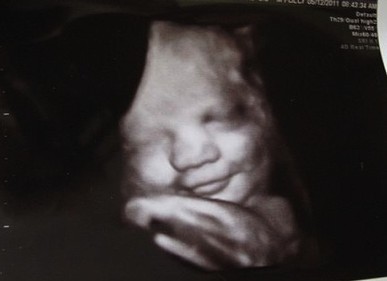

Mediante ecografías en cuatro dimensiones, Campbell consiguió imágenes de bebés sonriendo en el vientre materno. La polémica gira en torno a la auténtica naturaleza de estos gestos. Así, mientras algunos autores creen que son simples actos reflejos, otros defienden que pueden tener un significado emocional.

Ecografía. Bebe sonriendo